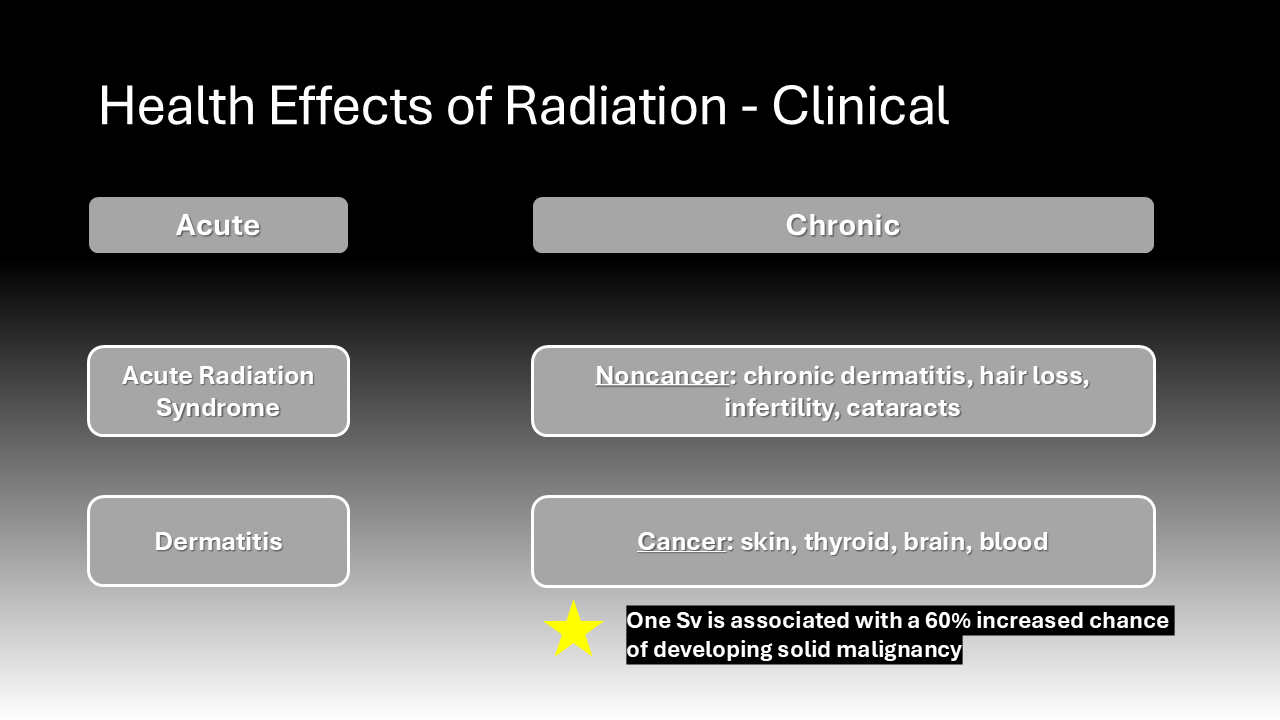

Health Effects of Radiation Exposure

The health effects of radiation exposure have been known since the immediate years following the introduction of X-ray technology when there was noted to be an increase in incidence of cancers among workers.11 More recent molecular research elucidates the mechanism by which radiation leads to deleterious effects. Ionizing radiation causes DNA breakage and mutation directly and through the generation of free radicals.11 One study found that molecular markers of DNA damage and repair were increased among the lymphocytes of patients and hospital staff immediately post-operatively when fluoroscopy was used.12 This resulting genetic instability may either kill a cell or cause it to become cancerous.12 The clinical effects of radiation exposure depend on the dose and duration of exposure. High doses can lead to severe skin damage and acute radiation syndrome, almost all exposure in healthcare involves low doses over long periods.4 While chronic exposure to low doses of radiation can lead to non-cancer effects such as dermatitis, cataracts, and infertility, the focus of this paper is on the cancer effects.6 Most quantifications of cancer risk due to radiation derive from studies on the impact of atomic bombs. Data from Hiroshima and Nagasaki, Japan, demonstrated that radiation exposure increases the risk of a variety cancer types, specifically skin, thyroid, brain, and blood cancers.7 Data from survivors of the atomic bombs was extrapolated to estimate that an exposure of 10 mSv confers a 1 in 2,000 risk of developing cancer of any origin.7 Studies of radiologists in the 1950s further substantiated the link between radiation exposure and the previously mentioned cancer types.13